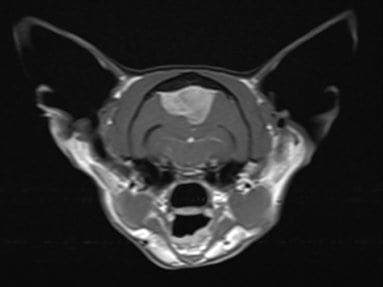

So, Henry was put into the hospital’s state-of-the-art MRI scanner which revealed that he had a large mass pushing on his brain. Specialist interpretation of the MRI images showed that a tumour called a meningioma was the most likely culprit.

Henry was quickly rushed to an operating theatre where a large team of surgeons and nurses undertook a ‘craniotomy’ surgery – the surgical removal of part of his skull to successfully remove the offending meningioma. A state-of-the-art titanium mesh was then used to repair Henry’s head, acting as part of his skull. This complex and precise operation took over two hours.